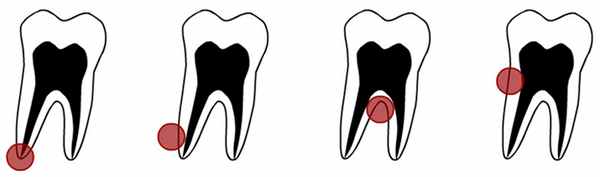

- радикулярная – киста, расположенная на корне зуба, развивается как осложнение хронического периодонтита и бывает апекальной (расположенной на верхушке корня) или латеральной периодонтальной (прилежит к боковой поверхности корня)

Радикулярные (одонтогенные воспалительные) кисты образуются на корнях зубов вследствие патологических процессов, распространяющихся за верхушкой корня. По расположению радикулярные кисты могут быть апикальными (корневыми), латеральными (боковыми), апико-латеральными и межкорневыми.